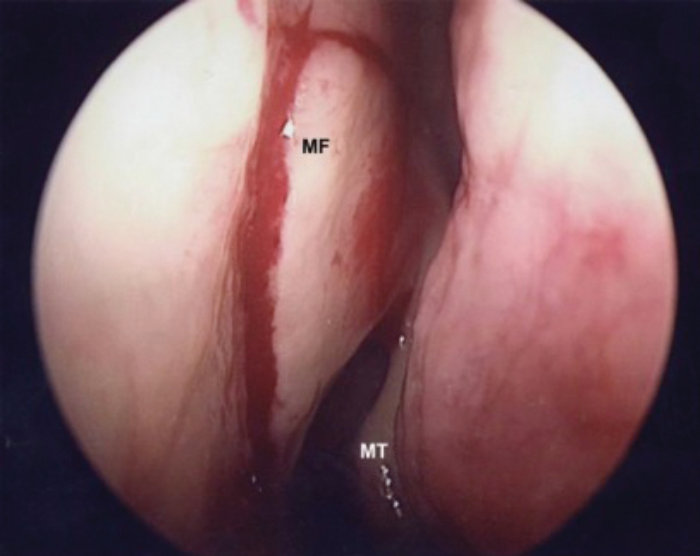

MT - Middle Turbinate MF - Mucosal Flap Marking

Figure 1. Mucosal incision in the lateral wall 8mm above, 8mm anterior to middle turbinate.